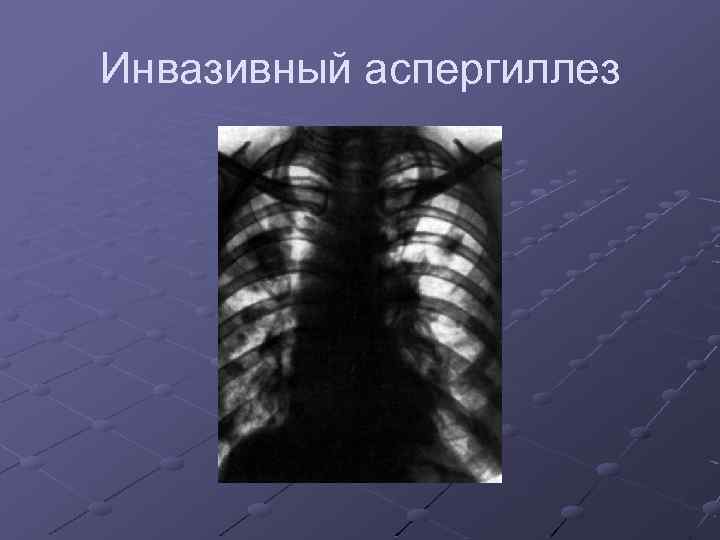

Раздел: Необычные решения